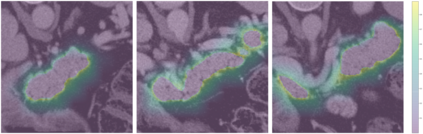

Transformer-based neural networks have surpassed promising performance on many biomedical image segmentation tasks due to a better global information modeling from the self-attention mechanism. However, most methods are still designed for 2D medical images while ignoring the essential 3D volume information. The main challenge for 3D transformer-based segmentation methods is the quadratic complexity introduced by the self-attention mechanism \cite{vaswani2017attention}. In this paper, we propose a novel transformer architecture for 3D medical image segmentation using an encoder-decoder style architecture with linear complexity. Furthermore, we newly introduce a dynamic token concept to further reduce the token numbers for self-attention calculation. Taking advantage of the global information modeling, we provide uncertainty maps from different hierarchy stages. We evaluate this method on multiple challenging CT pancreas segmentation datasets. Our promising results show that our novel 3D Transformer-based segmentor could provide promising highly feasible segmentation performance and accurate uncertainty quantification using single annotation. Code is available https://github.com/freshman97/LinTransUNet.